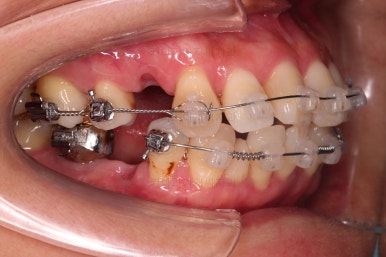

적절한 시점에 유치를 뽑아내고 남은 공간을 줄여나갑니다.

아래쪽 임플란트는 움직이지 않기 때문에 해당 치아를 기준으로 다른 치아를 모두 셋팅해야 하는 매우 난이도 높은 치료가 진행되었습니다.

발치 공간 앞뒤 치열을 당겨주어 공간을 줄여 나갑니다.

자연스레 입은 들어가게 될 것이고요.

임플란트는 크기가 작았으므로 교합을 위해서는 어쩔 수 없이 해당 부위에 틈이 남을 수 밖에 없었고요.

남은 틈은 임플란트 상부 보철을 재제작하면서 조절을 하기로 했습니다.